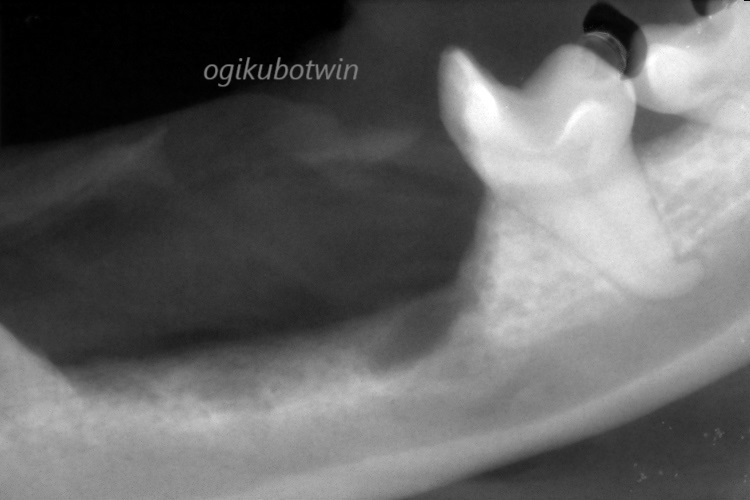

まず全身麻酔下にて右上顎第三前臼歯(奥歯)、第四前臼歯、左下顎第一後臼歯、第二後臼歯、第三後臼歯を歯周病のため抜歯しました。

問題の左下顎の腫瘍は採材して病理検査に提出しました。

腫瘍は粘膜のマージンを5㎜確保し、念のため背側の下顎骨の一部を切除しました。